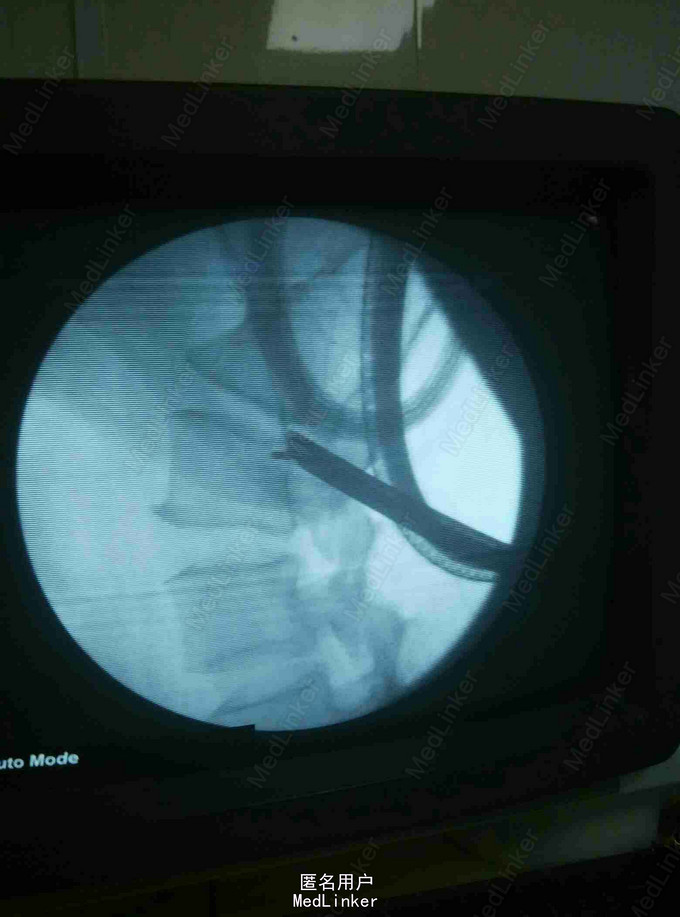

腰痛伴左下肢疼痛麻木3年

椎间盘突出穿破后后纵韧带游离到硬膜囊背侧

腰椎间盘突出,腰椎间孔镜治疗

术后症状明显缓解